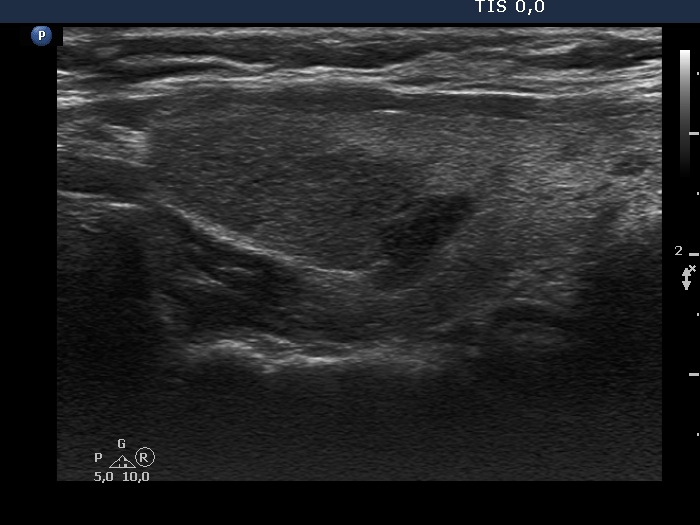

First examination (first, third and fifth rows of images):

Ultrasonography. The thyroid was echonormal and contained multiple inhomogeneous, partly blurred hypoechogenic and moderately hypoechogenic discrete lesions. Multiple lymph nodes were found on both sides of the neck.